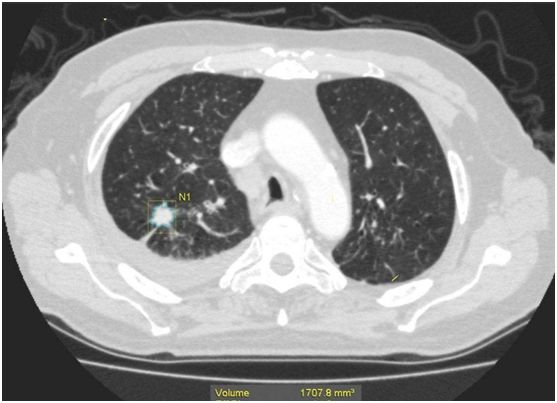

其实“肺部结节”不是疾病的学名,是指在拍片时看到的比较小的阴影,有良性、恶性之分,根据结节的密度不同,可以分为磨玻璃结节、部分实性磨玻璃结节和实性结节,这三类结节中恶性病变所占比例分别是18%、63%和7%。

医生会根据结节的生长方式、边缘形态、内部密度高低、周围血管结构来综合分析判断结节的性质,但是早期肺癌的诊断仍然是比较困难的。定期复查肺部发现结节的生长速度、内部结构、边缘改变等都是判断肺部结节良恶性的重要依据。

如果肺部结节发现有边缘有毛刺和分叶,周围有胸膜的牵拉,就要高度怀疑肺癌的可能。